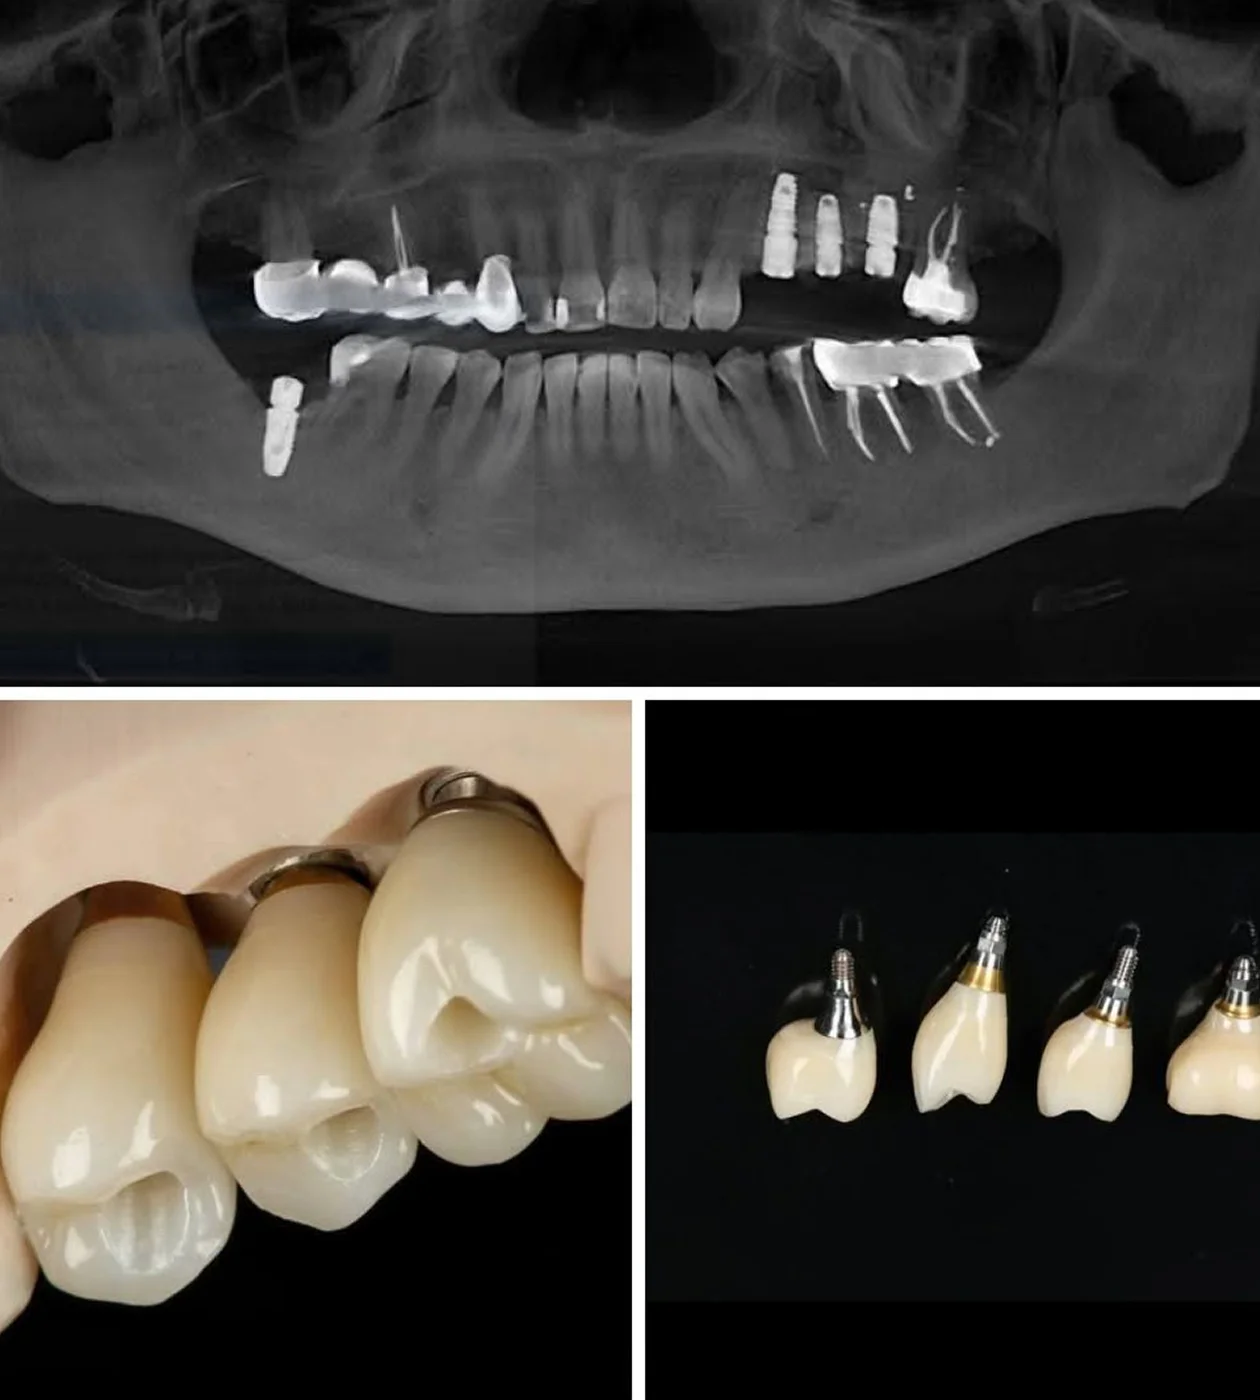

Дентальна імплантація

Заміщення відсутніх зубів за допомогою дентальної імплантації з подальшим протезуванням.

Відновлення функції жування після втрати зубів

Протезування проводиться з використанням цифрових технологій та з сучасних матеріалів (циркон).

ПРОТЕЗУВАННЯ НА ІМПЛАНТАХ

При відсутніх зубах проводимо заміщення дефектів за допомогою дентальних імплантів та протезуванням цирконієвими коронками.